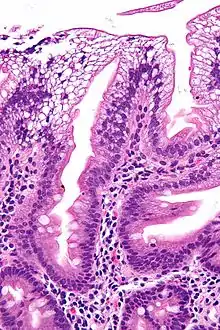

![]() صورة مجهرية تبين الخلايا المعوية الماصة والسيتوبلازم واضح (بسبب تراكم الدهون) وهو ما يميز فقد البروتين الشحمي بيتا من الدم، خزعة من الاثنا عشر مصبوغة بالهيماتوكسيلين واليوزين. صورة مجهرية تبين الخلايا المعوية الماصة والسيتوبلازم واضح (بسبب تراكم الدهون) وهو ما يميز فقد البروتين الشحمي بيتا من الدم، خزعة من الاثنا عشر مصبوغة بالهيماتوكسيلين واليوزين. | |

ويكون هناك غياب لصميم البروتينات الشحمية ب. ويمكن رؤية فراغات تحتوي على دهون في الخلايا المعوية في خزعة الأمعاء. قد يؤدي هذا الاضطراب أيضا إلى تراكم الدهون في الكبد (تشحم كبدي). لأن الخلايا الظهارية في الأمعاء تفتقر إلى القدرة على وضع الدهون على الكيلوميكرونات، فتتراكم الدهون على سطح الخلية، مما يؤثر على وظيفة الخلايا الضرورية للامتصاص السليم.